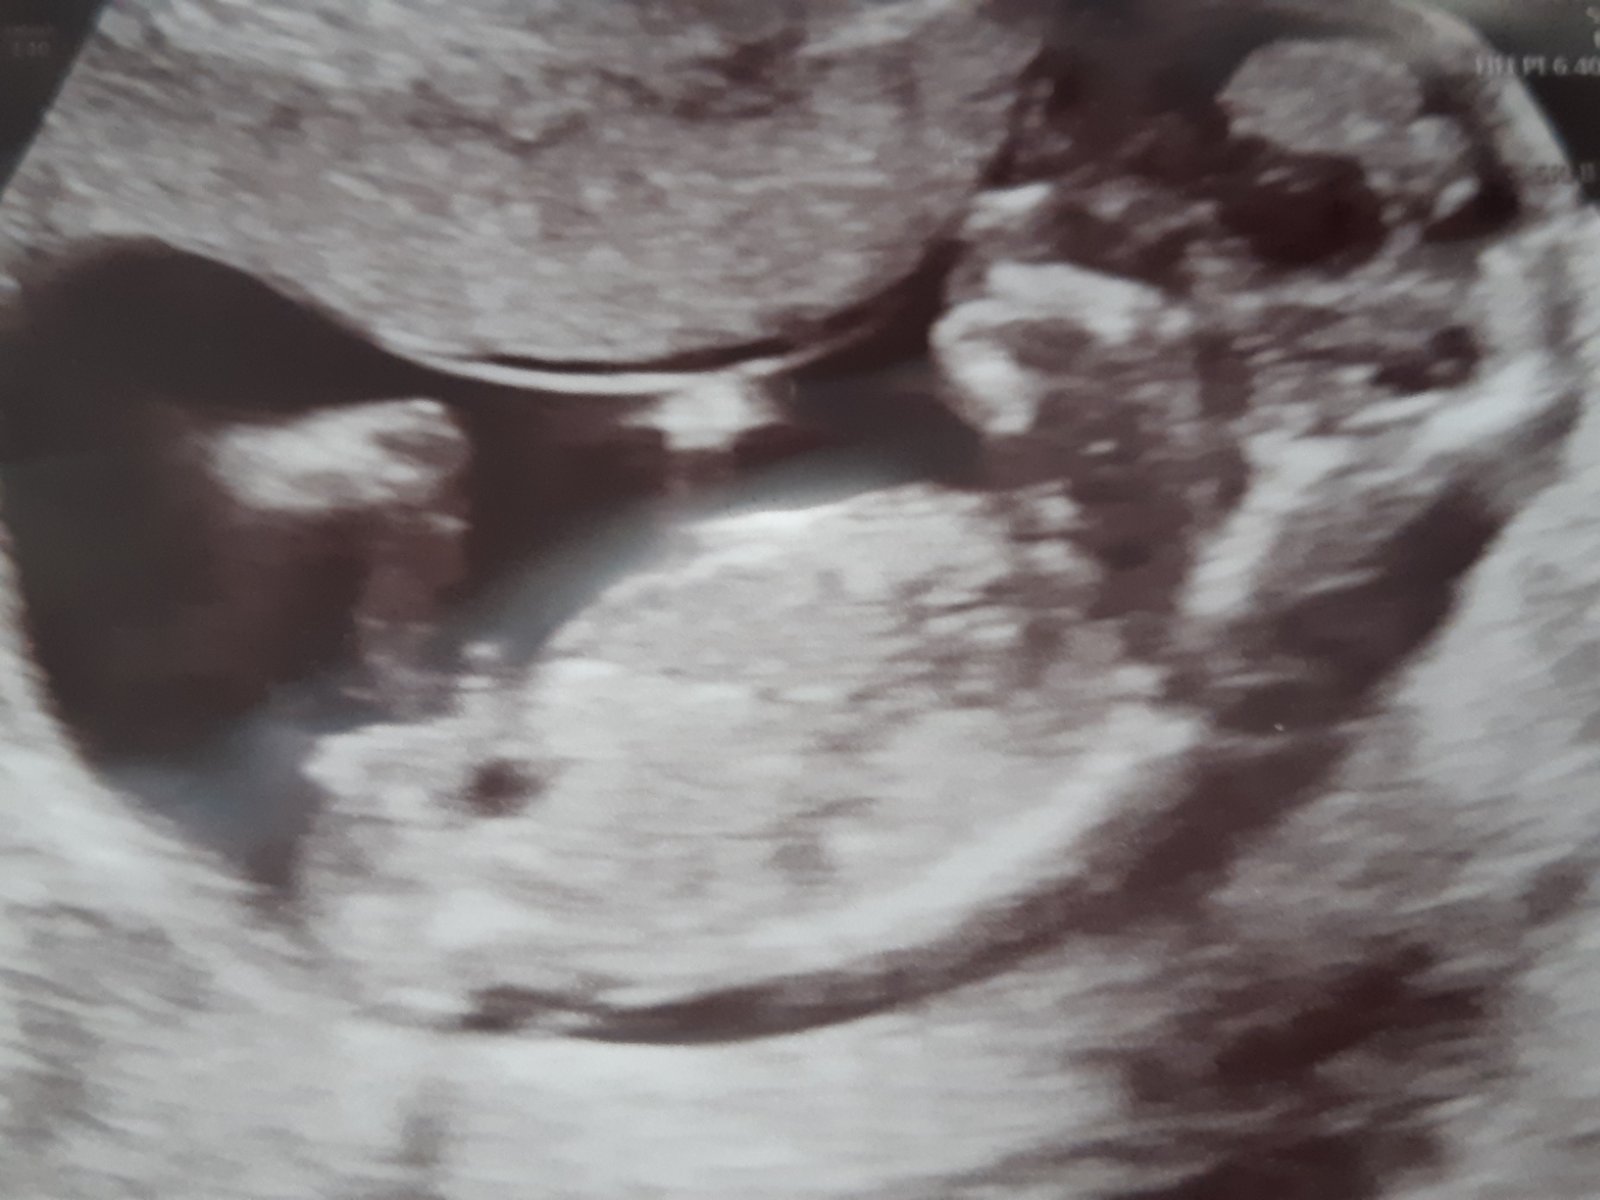

@mikejla_a dobrý den,chtěla jsem se zeptat jak to dopadlo s tím ultrazvukem? Co to nakonec bylo? Mam to dost podobne, na jedné fotce to vypadá na holku a na druhé jde hrbolek nahoru jak na kluka. Moc dekuji.

@janagranada mame holcicku ❤️ klidne posli fotku ☺️